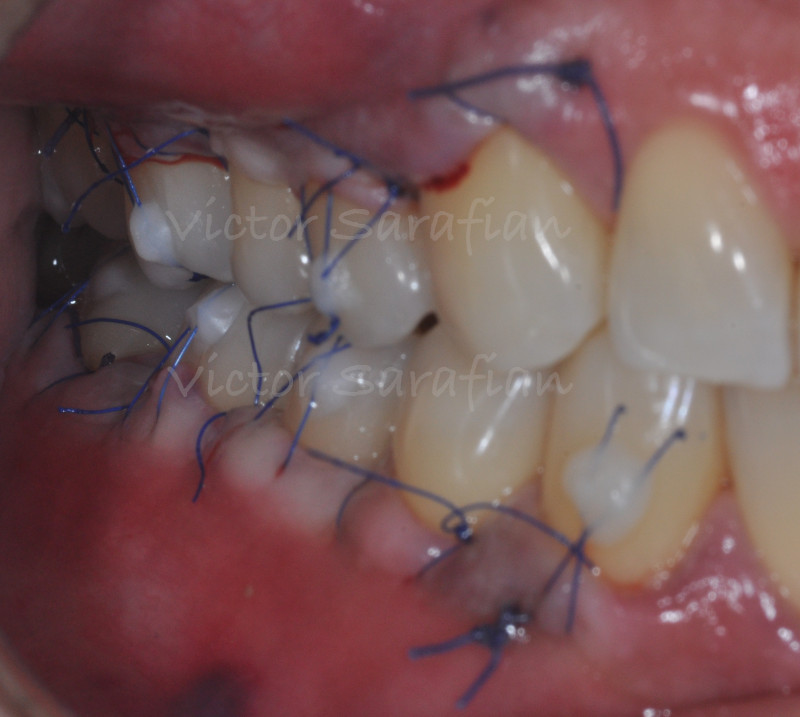

Par un jeu de sutures suspendues dont certaines sont collées au composite directement sur les faces vestibulaires des dents, l’ensemble lambeau et tissu conjonctif est déplacé coronairement, plaqué aux surfaces radiculaire préalablement préparées, et maintenu en position coronaire.

Certains points additionnels, ayant pour but d’optimiser le plaquage du lambeau sur les surfaces radiculaires, sont rajoutés au collet des dents et sont fixés sur les faces vestibulaire à l’aide de composite.